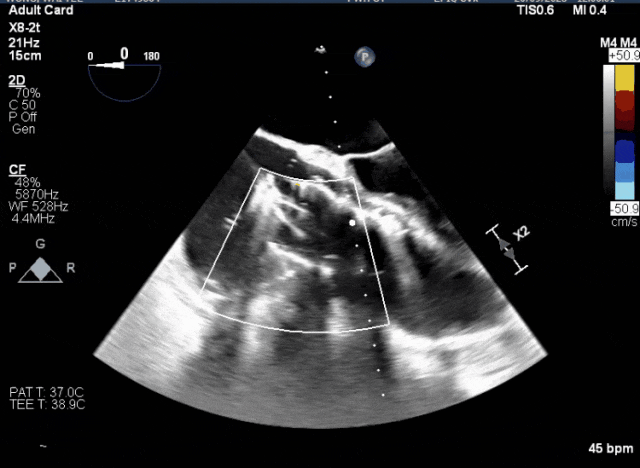

術中TEE成像困難,偽影干擾

術后DSA、超聲顯示人工瓣膜穩定性良好,瓣葉啟閉正常,無瓣周漏

術中TEE觀察夾持件的位置

術后DSA

術后超聲評估瓣膜穩定性良好,無瓣周漏